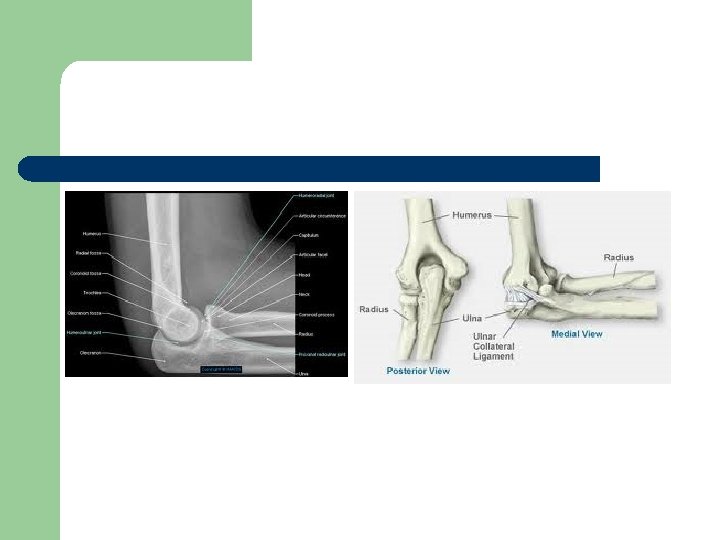

Art. Cubiti l Üç kemik arasında kurulu bir eklem olduğu için, art. composita’dır.

l Üç eklemden oluşur. 1. Art. humeroulnaris (ginglymus), 2. Art. humeroradialis (art. spheroidea), 3. Art. radioulnaris proximalis (art. trochoidea).

l Bu eklemin temel hareketleri fleksiyon ve ekstansiyon’dur. Ancak bu hareketler sırasında çok az rotasyon hareketleri de yapılır.